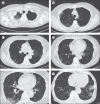

Findings: Among the 104 participants included in the final analysis, the median age was 68 years (IQR 47-75) and 54 (52%) were male. On admission, 43 (41%) participants were classified as asymptomatic, 41 (39%) as having mild COVID-10, and 20 (19%) as having severe COVID-19. At the end of observation, 33 (32%) participants were confirmed as being asymptomatic, 43 (41%) as having mild COVID-19, and 28 (27%) as having severe COVID-19. Serum lactate hydrogenase concentrations were significantly higher in the ten participants who were asymptomatic on admission but developed symptomatic COVID-19 compared with the 33 participants who remained asymptomatic throughout the observation period (five [50%] vs four [12%] participants; odds ratio 7·25, 95% CI 1·43-36·70; p=0·020). Compared with patients with mild disease at the end of observation, patients with severe COVID-19 were older (median age 73 years [IQR 55-77] vs 60 years [40-71]; p=0·028) and had more frequent consolidation on chest CT (13 [46%] of 28 vs nine [21%] of 43; p=0·035) and lymphopenia (16 [57%] vs ten [23%]; p=0·0055) on admission.

Interpretation: Older age, consolidation on chest CT images, and lymphopenia might be risk factors for disease progression of COVID-19 and contribute to improved clinical management.